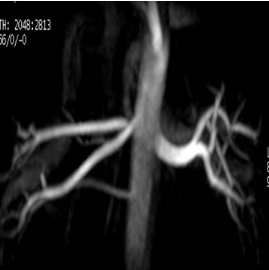

Inhance: 3D Velocity scan

Use Inhance 3D Velocity to acquire contrast-free angiography images with excellent background suppression at a shorter scan time in comparison to 3D PC. Typically used for renal and brain scans.

- Scan plane: For brain scans, select a sagittal scan plane to reduce the number of slices and thus the scan time. For renal scans, select an axial plane.

- Deposit an axial slab for renal scans.